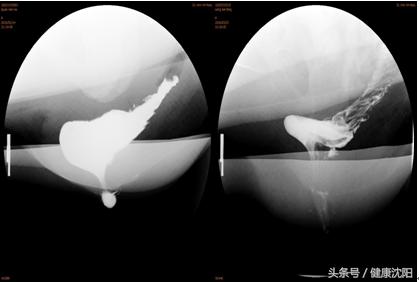

2.排粪造影

通过排粪造影检查可了解本病患者是否存在直肠肛管解剖结构的异常,从而筛选并指导患者下一步是否需行手术治疗,并评估手术方案。

出口梗阻性便秘的排粪造影图片